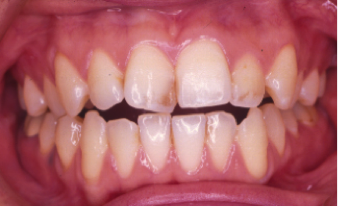

開咬(かいこう)

24歳/女性

悩み:前歯が噛めない

奥歯は噛み合っていても上と下の歯に隙間が空いてしまう状態

治療前

治療後

前歯で噛む事が出来ないとの悩みから来院された患者様で、開咬症例ではあるのですが突出傾向があったため、小臼歯4本抜歯をする治療方針で約三年ほどかかって治療いたしました。治療後にはきちんとものが噛めるようになり、約三年間の頑張りが報われましたと喜んで頂けました。